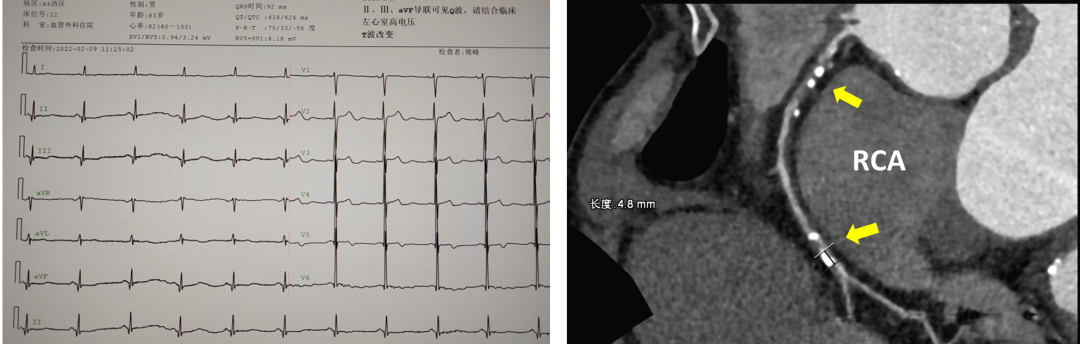

急性冠脉综合征:非ST段抬高性心肌梗死

胸闷加重伴阵发性胸痛

冠脉CTA:右侧冠状动脉中段重度狭窄;远段中度狭窄(50%)

心电图:Q波和T波改变

心脏彩超:节段性室壁运动异常,下壁心梗后改变,EF 41%